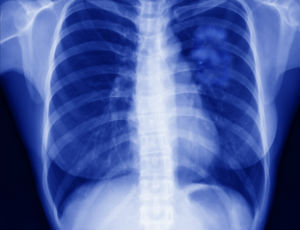

When she visited the ER in early 2015 doctors suggested she get a CAT scan. But instead of finding what they thought would be blood clots in her lungs, the doctors found a lump. After a succession of tests over months proved inconclusive, she kept pushing for an answer until doctors determined that surgery was necessary. When she awoke from surgery, she learned that her upper left lung tissue had been removed and she had been diagnosed with Stage 1a lung cancer, an early stage where the cancer is contained and hasn’t traveled to any surrounding tissues. She has been cancer-free since.

Lung cancer is the No. 1 cancer killer of women and one of the top cancers that affect African Americans. More than 106,000 American women are estimated to be diagnosed this year alone, according to the report.